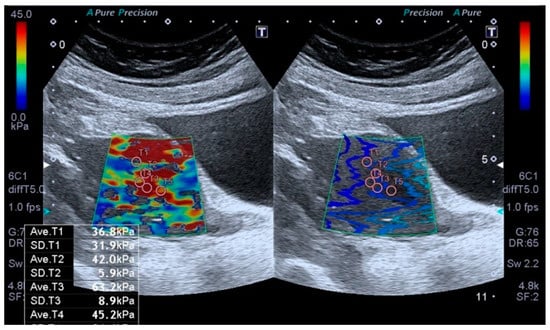

2.3. Elastography Analysis

All sonographic and elastographic examinations were performed by the same radiologist who has 12 years’ experience in genitourinary radiology. A digital sonography scanner (Aplio i500, Canon Medical Systems, Tustin, CA, USA, equipped with a 3–5 MHz convex probe) was used to perform real-time tissue elastography which is a shear wave-based technology. The uterus was scanned in the coronal and longitudinal projections. The endometrial thickness was measured by B-mode ultrasound in the sagittal plan. Elastography examinations were performed by holding the breath and lightly touching the probe skin to minimize movement artifacts. After obtaining conventional US images, the target area was determined, and measurements were taken from the region of interest (ROI) (Figure 1).

The region of interests (ROIs) were adjusted to include maximum homogeneous and thick tissue to avoid the ROI bias. The fixed ROI box size of our study was 1–0.5 cm. The elastographic images that exhibited color homogeneity were selected for elastographic data analysis. Five regions of interest were set for the SWE images, which were displayed as a translucent color map superimposed on the corresponding B-mode image. Tissue elasticity measurements were made using a map with a color range from dark blue to red (soft to hard). The stiffness value was obtained to evaluate the stiffness of the endometrium quantitatively. To evaluate endometrial stiffness, 5 valid measurements were taken from each patient’s endometrial lesion, and their average was calculated. The results were expressed in kPa. From the five measurements, the mean, and IQR/median values were calculated, and only measurements with IQR/median ratios ≤30% were considered acceptable. All US images were sent to the workstation and archived in the picture archiving and communication system (PACS) (Sectra IDS 7, Sectra, Linköping, Sweden). The average time to obtain a reliable measurement was about 20–30 min.

Figure 1. Transabdominal ultrasound examination of the endometrium, including shear wave elastography (SWE). Placement of sample points of the region of interest (ROI) in the endometrial lesion for SWE measurements.